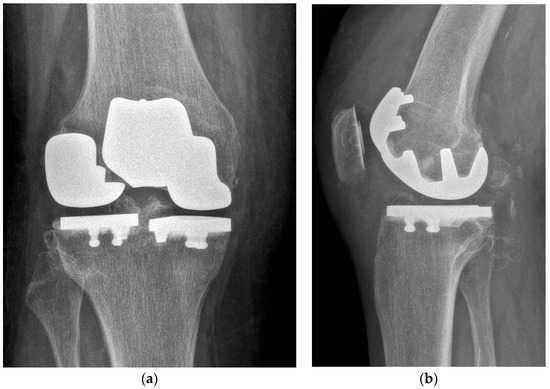

One-Stage Tricompartmental Hypoallergenic UKA for Tricompartmental Osteoarthritis: A Case Report

2. Case Description